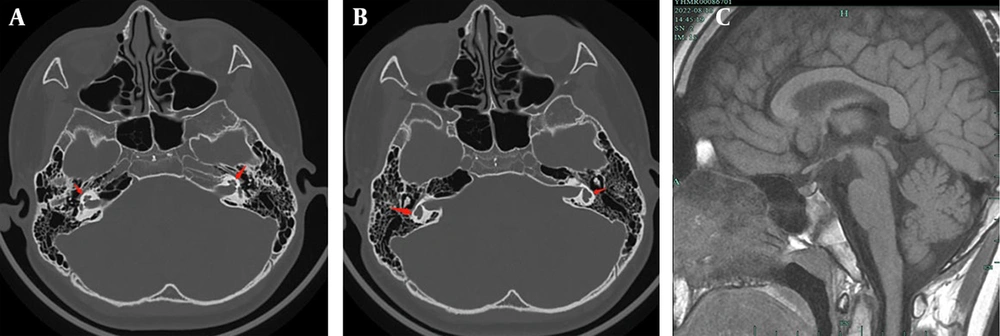

Scrotal ultrasound demonstrated decreased testis sizes (right side volume: 1.4 × 0.7 × 1.1 cm; left side volume: 1.7 × 0.7 × 1.1 cm). Pituitary magnetic resonance imaging (MRI) and cochlear computed tomography (CT) did not reveal any abnormalities, although the semicircular canals appeared short and thick (Figure 1).

In this report, we describe a patient presenting with a combination of KS and WS type II. The patient exhibited congenital sensorineural hearing loss and pigmentary abnormalities (blue iris) without Hirschsprung disease, which are the primary characteristics of WS type II. He also manifested certain characteristics of KS, including HH and anosmia. Genetic testing revealed a novel heterozygous mutation in the coding sequence of exon 3 of SOX10. SOX10 belongs to the SOX [SRY-related high-mobility group (HMG) box] family of transcription factors, encoding a 466-amino-acid protein that contains a DNA-binding motif known as the HMG domain (10). This is essential for developing and differentiating various cell lines. SOX10 dysfunction hinders NC into olfactory ensheathing cells (OECs), melanocytes, intestinal ganglion cells, and numerous autonomic and sensory ganglion cells, leading to various clinical manifestations. In melanocytes, SOX10, cooperating with PAX3, binds to the MITF promoter to activate MITF and then activates the expression of dopachrome tautomerase (Dct) and tyrosinase (Tyr), which play an important role in melanin synthesis (1, 11). Melanocyte dysfunction results in abnormal pigmentation of the hair, skin, and irises. Furthermore, melanocytes play a crucial role in inner ear homeostasis (12). SOX10 is expressed in the otic vesicle, restricted to the epithelium and glial cells in the mouse inner ear (13, 14). This is consistent with our patient's sensorineural hearing loss and the observed semicircular canal abnormalities, as recent studies have reported hypoplasia/dysplasia or agenesis of the semicircular canals in patients with SOX10 mutations (15). SOX10 also plays a critical role in OECs, which are essential for the development of the olfactory bulb and the migration of GnRH cells (16). The patient's anosmia and HH are directly linked to SOX10's role in these processes. In mice with a SOX10 mutation, OECs were nearly absent, and they displayed de-fasciculation and misrouting of nerve fibers, as well as impaired migration of GnRH cells (2).